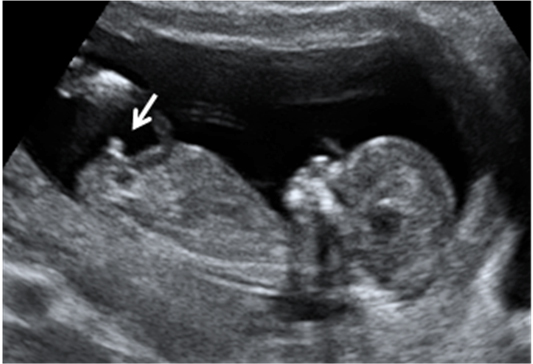

La ecografía Doppler permite comprobar el flujo sanguíneo en el feto y en el cordón umbilical, y así diagnosticar algunas enfermedades o malformaciones cardiacas, entre otras cosas.

Ecografía Embarazo 2D y 3D Semana 12 - PRUEBAS DIAGNÓSTICAS